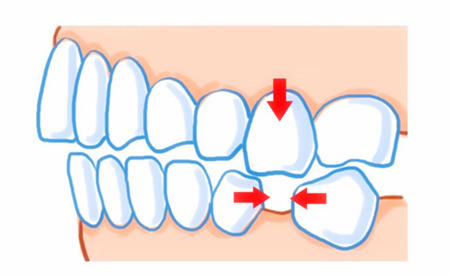

什么叫牙齿移位呢?牙齿完好地萌出长大,咬合咀嚼都没有问题,已建立好稳定的咬合及邻面接触关系,但因为牙周支持组织被破坏,或因外力、咬合力等因素导致牙齿位置发生改变,这种情况就称之为牙齿移位。牙齿移位可能造成牙根松动,牙缝扩大造成食物嵌塞。牙齿移位是什么原因造成的呢?引起牙齿移位的主要因素如下。相关阅读:正畸期间牙齿移位的不良影响

单颗牙缺失导致移位

正常的与邻牙的接触关系,良好的牙齿形态及牙尖斜度,牙列的完整性,咬合力与牙齿周围唇颊舌肌力的平衡,长期不良的咬物习惯等施加于牙齿上的各种力的改变是引起牙齿发生移位的重要因素。如其中较常见的例子是牙齿缺失后,长期没有进行修复治疗,可导致邻牙向缺牙间隙倾斜,对颌牙齿伸长,发生牙齿移位。

由于颌面部受到外力撞击或咬硬物可导致牙齿移位,多见于前牙。相关阅读:西安牙齿缺失要如何预防